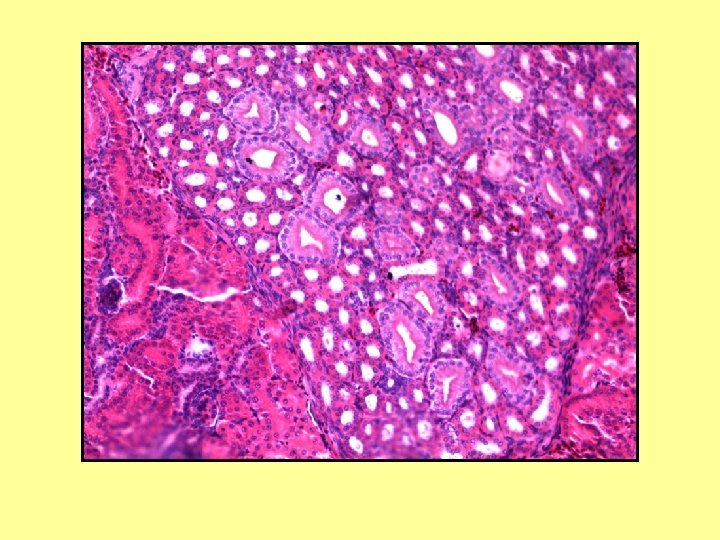

Tek Katlı Kübik Epitel Preparat: Tiroid Kesit: Enine Boya: Hematoksilen-Eozin

Tiroid Folikülü Kolloid Tek Katlı Kübik Epitel